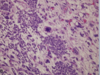

What tumor type is shown here?

* key features?

Papillary Adenocarcinoma

• MULTIFOCAL, Granular appearance is key

hemorrhage and necrosis may also be seen here but is less common than renal cell carcinoma

What is shown here?

• What are the KEY features?

- Well-circumscribed, often with distinct fibrous capsule

- PAPILLARY - little finger like projections in the cellular arrangment

- Have papillary FIBROVASCULAR CORES (seen in center)

- Foamy macrophages (clear cells) in papillary cores and intracellular hemosiderin are sensitive/specific features